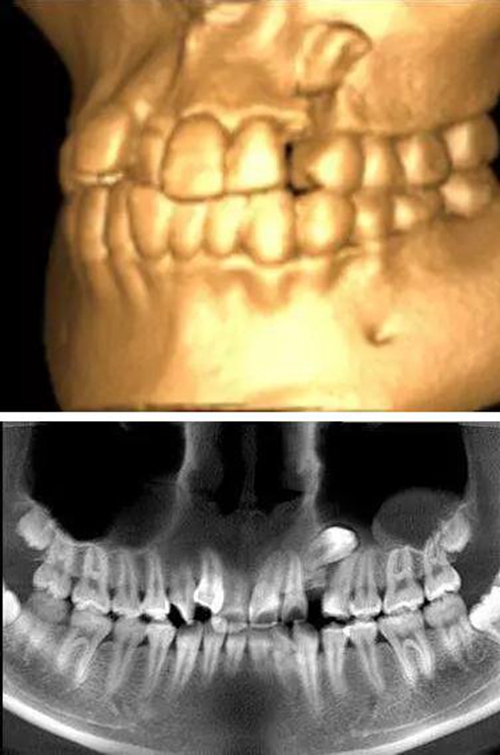

本案:患兒,女,14歲,因牙齒矯正來院,檢查見83滯留,43未見萌出,拍片發(fā)現(xiàn):43埋伏阻生于31、41、42根尖下方,按照正畸診療計(jì)劃,擬行43拔除術(shù)。

口腔牙列照片

全景片